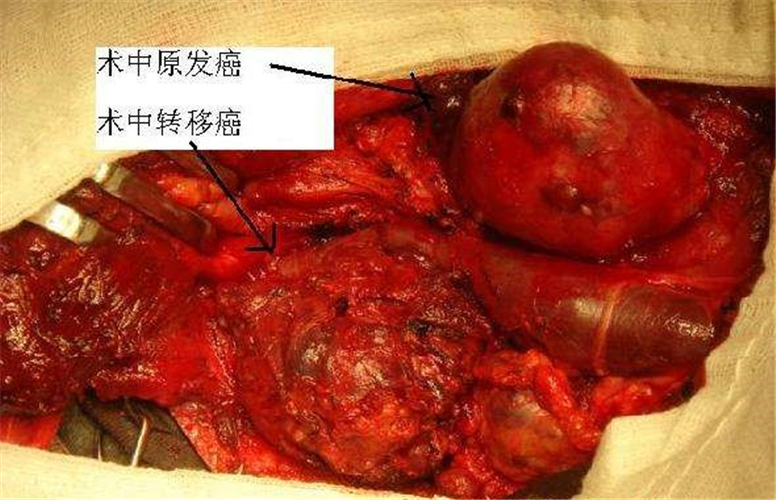

晚期甲狀腺癌手術